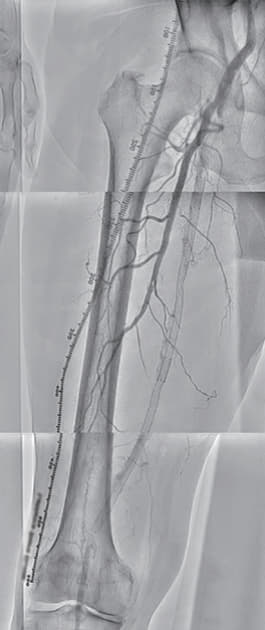

過去にSFAに留置された総長約35 cmの3本のBMSの入口部からの閉塞(動画1)近位端はSFA入口部から1 cm程度の健常部があり、遠位端は膝窩動脈近位部(P1)で側副血行流入部まで1 cmの余白がある。対側山越えアプローチで6 Frガイディングシースを挿入して治療を開始した。ステント外を通過しないように0.035 inchのガイドワイヤーを選択すると容易に遠位部へ到達することが出来た(動画2)。この手ごたえから血栓性病変であることが予想された。持続吸引カテーテルを用いて何度か血栓吸引を行ったが血流は再開しなかった(動画3)。

血管内超音波(IVUS)を行うとガイドワイヤーはステントの中心部を通過していたが、予想通り病変内には大量の血栓が堆積していた(動画4)。7 mmのバルーンで拡張したのち、ステント遠位端より2 cm程度離れた遠位の健常部にhealthy landingをとって(動画5)バイアバーン® ステントグラフト6 × 250 mmを留置した。近位側はステント近位端より1 cm程度離れたSFA入口部の健常部にhealthy landingをとって(動画6)バイアバーン® ステントグラフト7 × 150 mmを留置した。上下端とも既存のステントより外側にランディングをとること、ステントグラフトの電子添文の「使用上の注意」にあたる主要な側枝に注意して、大腿深動脈(DFA)や側副血行の流入部にかからないよう留意した。後拡張は血栓の上下方向へのprotrusionを防ぐ目的で先に遠位端、近位端の順に高圧バルーンで拡張し健常部血管壁への圧着をとった。ステントグラフトの中間部への後拡張はそのあとに続いて行った。最終造影で末梢まで塞栓がないことを確認して終了した(動画7)。